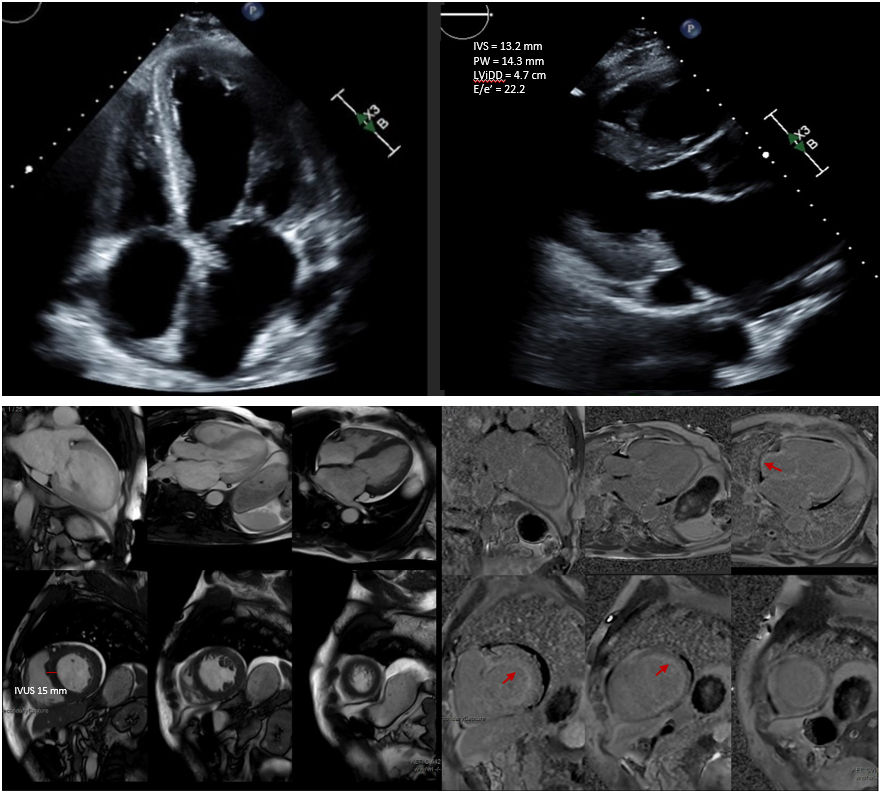

Methods/workup: Laboratories are shown in Table 1 and were notable for a serum free light chain ratio of 0.14. Transthoracic echocardiogram (figure 1) revealed a left ventricular (LV) ejection fraction of 33% with increased LV wall thickness and severe bi-atrial enlargement. Bone marrow biopsy revealed 2% lambda restricted plasma cells without evidence of amyloid deposits; metastatic bone survey was negative. A fat pad biopsy and endomyocardial biopsy stained negative for amyloid with Congo red. Cardiac MRI showed diffuse, circumferential subendocardial late gadolinium enhancement, most compatible with cardiac amyloidosis (figure 2). The patient also had a chest CT scan that demonstrated a few patchy nodular pulmonary infiltrates. Given his extensive negative workup, he was referred to pulmonary and endobronchial biopsy was positive for amyloid on Congo red staining (figure 3). Biopsy tissue typing revealed Lambda subtype AL amyloidosis.